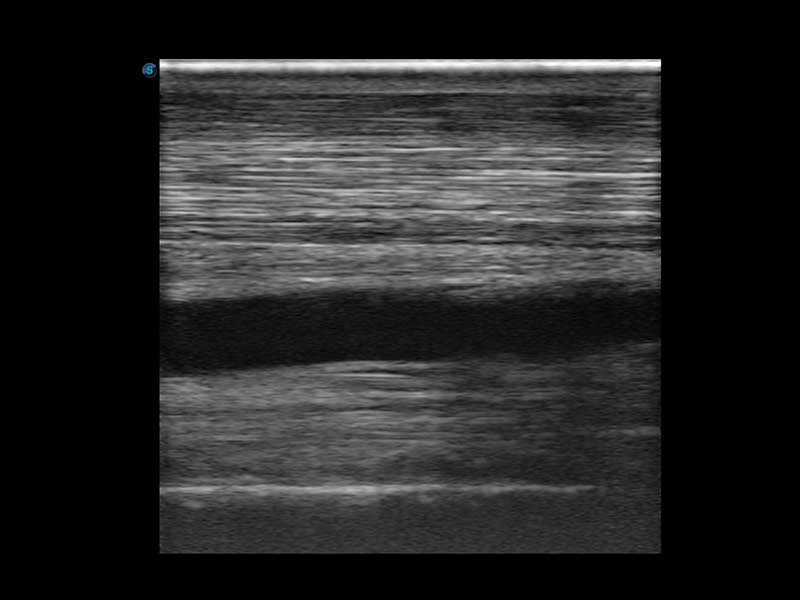

Az X Series Vet platform egy laptop kialakítású színes Doppler ultrahangrendszer, amely kiemelkedő képalkotó technológiáival van felszerelve, és professzionális állatorvosi szoftvereket kínál a kis kedvtelésből tartott állatoktól a nagy haszonállatokig. Kristálytiszta képalkotása és gördülékeny munkafolyamata új, továbbfejlesztett vizsgálati élményt biztosít, amely a magabiztos diagnózishoz szükséges pontosságot nyújtja.

Mivel az X Series Vet a SonoScape legújabb képalkotó technológiáit alkalmazza a nagy felbontású és mély penetrációjú képek előállításához, nagy mennyiségű diagnosztikai információ jeleníthető meg az ultrahang képernyőn. A továbbfejlesztett képminőség gyorsabb és pontosabb vizsgálatokat tesz lehetővé bármely állatfaj esetén.

A hatékonyságot, egyszerűséget és sokoldalúságot ötvözve az X Series Vet kiváló választás lógyógyászati vizsgálatokhoz. Speciális transzducerekkel és ló specifikus szoftverekkel felszerelve könnyedén készít lenyűgöző képeket az olyan alapvető alkalmazási területeken, mint az MSK, a reproduktív szervek vizsgálata, valamint a megfelelő penetrációt biztosítja hasi és kardiológiai vizsgálatokhoz is.